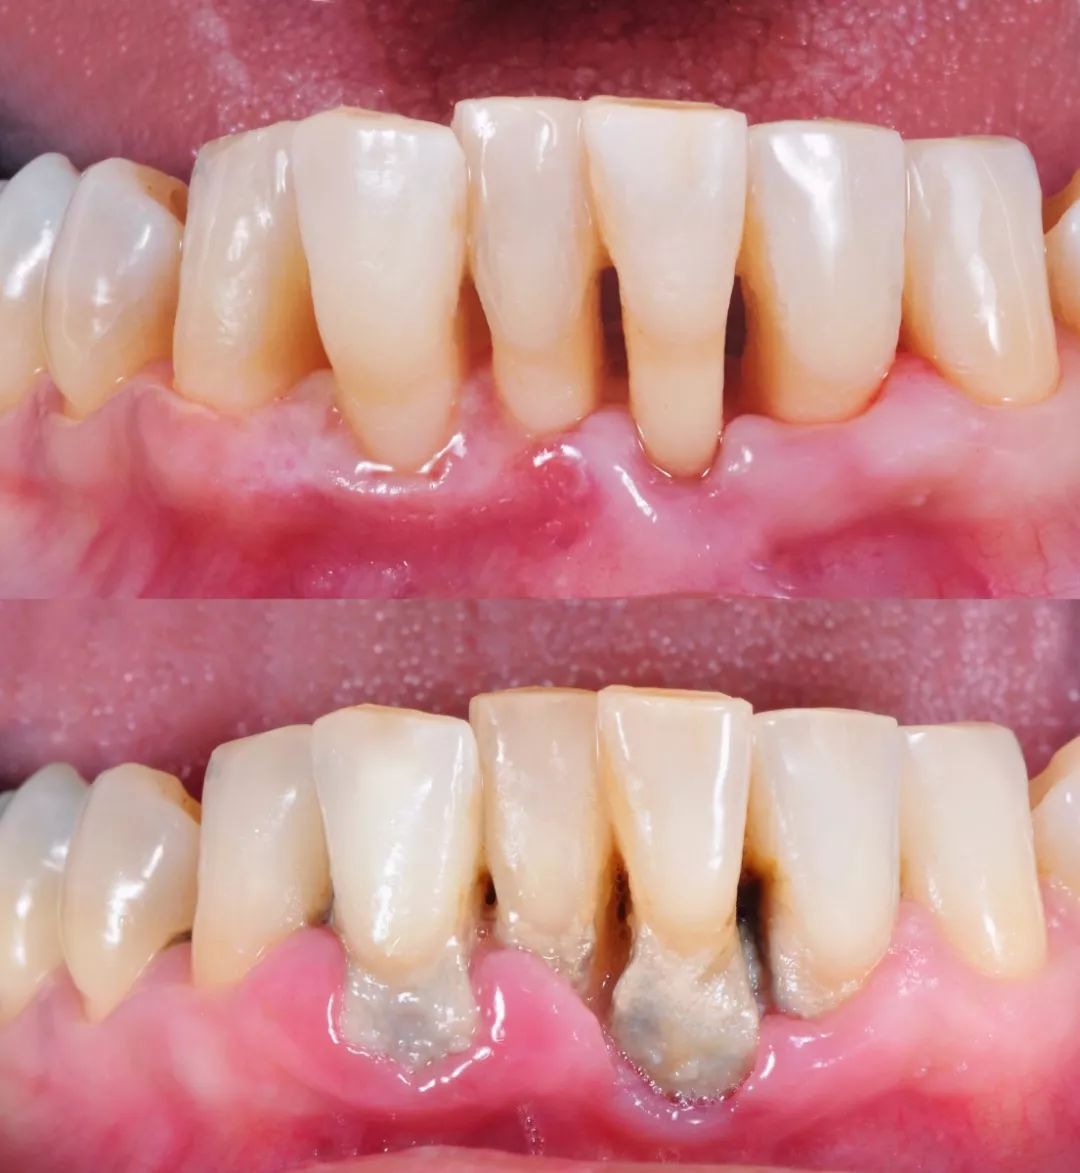

Thorough Removal of Plaque and Calculus: Addresses deep cleaning issues that brushing cannot handle, eliminating the primary cause of periodontal diseases .

Prevention and Treatment of Gingival Diseases: Effectively controls gingivitis and periodontitis, reducing problems like gingival bleeding and halitosis (bad breath) .

Maintenance of Alveolar Bone Health: By controlling inflammation, it helps maintain the height of the alveolar bone, preventing tooth loosening and loss .